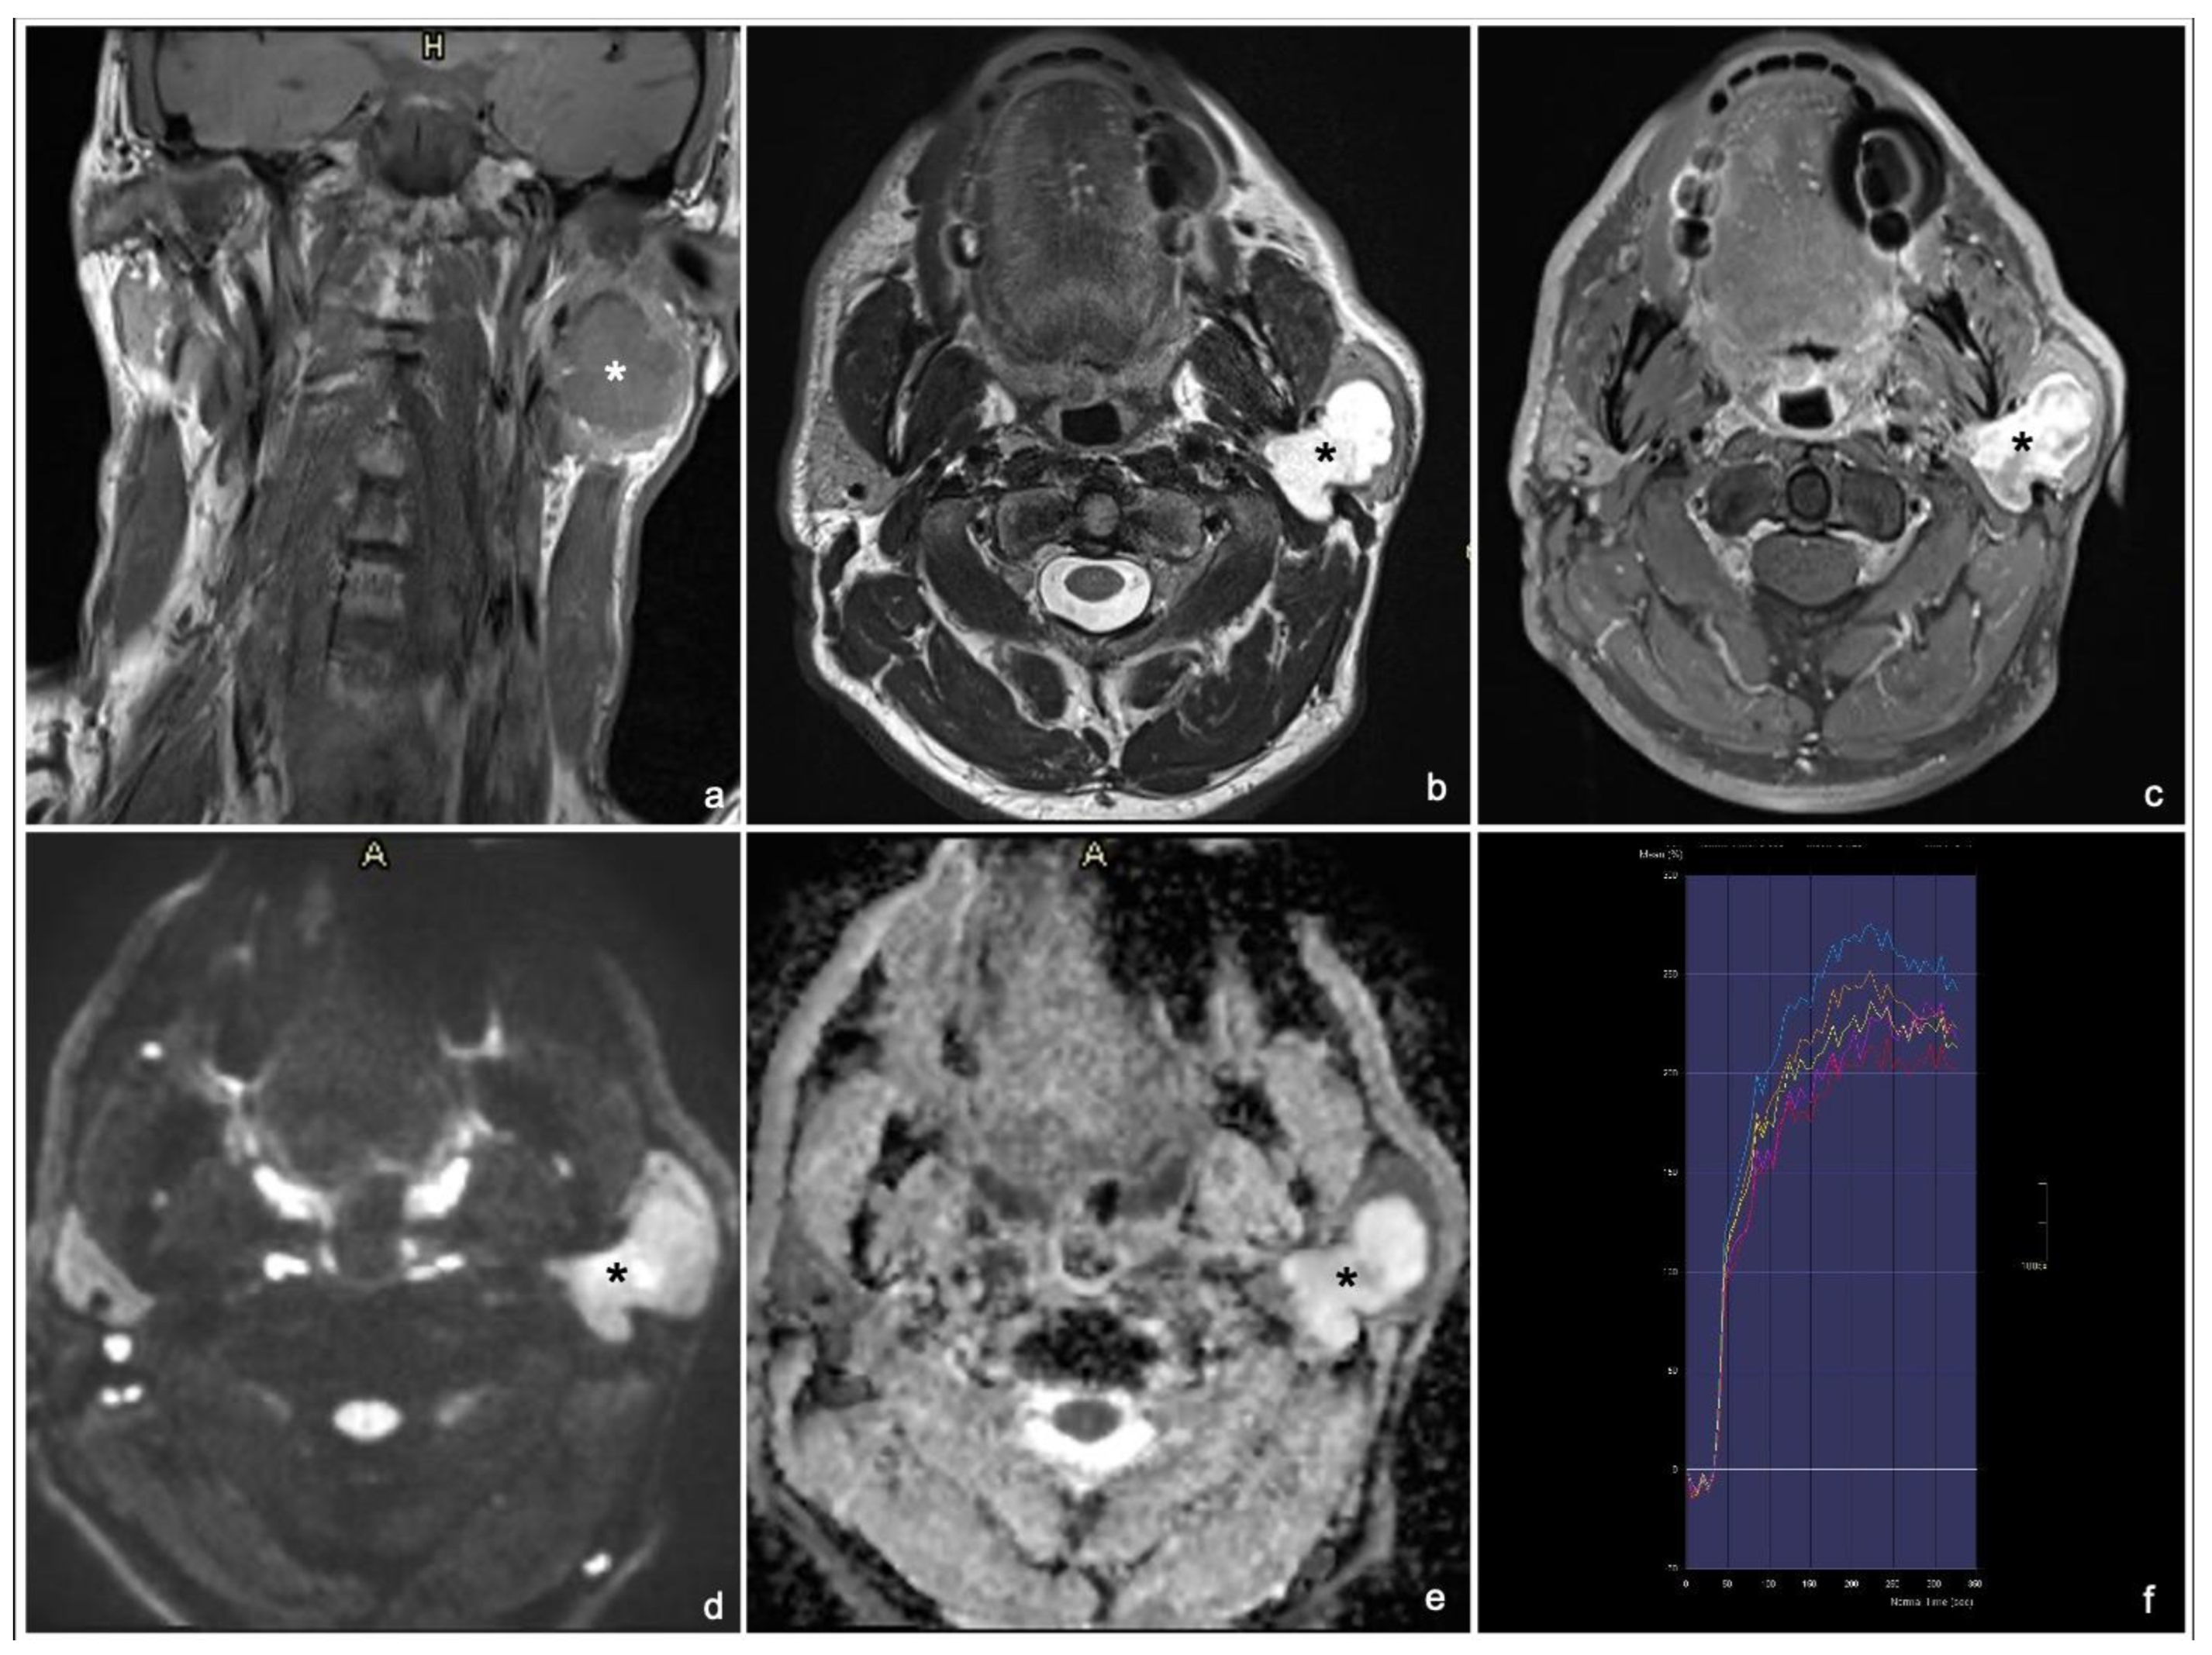

Typical MRI appearances of a pleomorphic adenoma, a Warthin tumor and a malignant tumor are shown in Figure 1, Figure 2 and Figure 3.

Figure 2. 65 years old woman with Warthin tumor of the right parotid gland: coronal T1 TSE (a), axial T2 TSE (b), late T1 TSE FS + Gd (c), DWI and ADC map (d,e) and DCE signal intensity-time S(t)-curve type B (f). * tumor. The lesion is characterized by T1 hyperintense intratumoral cysts (arrow) (a) and low enhancement on late T1 post-contrast sequence (normalized late T1 + Gd SI < 2) with isointensity to the normal parotid tissue with a thin peripheral rim enhancement (“ghosting sign”) (c).